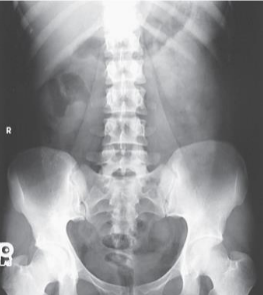

Left lateral decubitus

In an AP Abdomen, left lateral decubitus, the CR is

horizontal and perpendicular to 2 inches above iliac crest

The IR orientation in an abdomen left lateral decub is

CW to the patient

If the abdomen is too wide to include both flanks on one image, adjust patient and IR height to include ___ ___ when intraperitoneal fluid

side down

In decubitus for chest and abdomen, you would mark the

elevated side